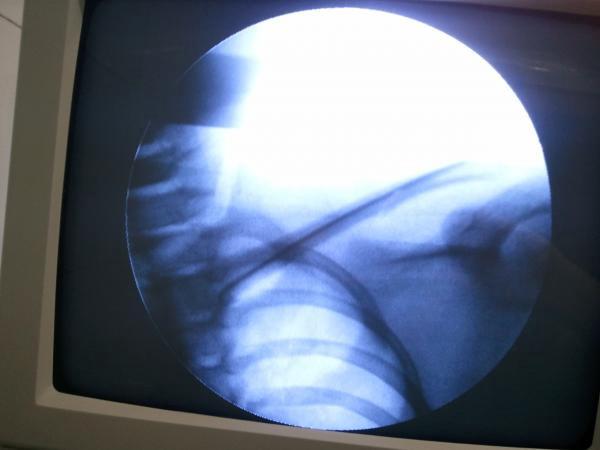

九岁儿童锁骨骨折,闭合复位经皮内固定。

患儿九岁,跌倒伤右肩入院。查:右肩下垂,头偏向右侧,下颌转向左侧,左手托右肘。锁骨上凹饱满,压痛,骨擦感。DR:右锁骨骨折。入院完善检查,手法复位经皮內固定。